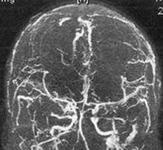

顱內靜脈竇閉塞性顱高壓